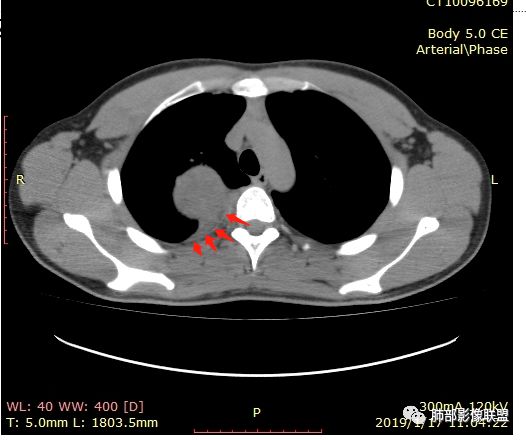

脏层胸膜主要由支气管动脉和肺动脉供血,壁层胸膜主要由支气管动脉,胸廓内动脉、肋间动脉供血

如果是肋间动脉,就不可能是脏层胸膜,可以是壁层或者纵膈

但是这个病人,肋间动脉供血吧,我倾向胸膜

边缘光滑,宽基底与胸壁相连,跨叶裂,叶裂稍前推,血管、支气管前移。

浅分叶

外上侧少量胸水

肋间动脉供血,强化尚均匀,逐步强化

张延军:

胸膜下脂肪间隙?